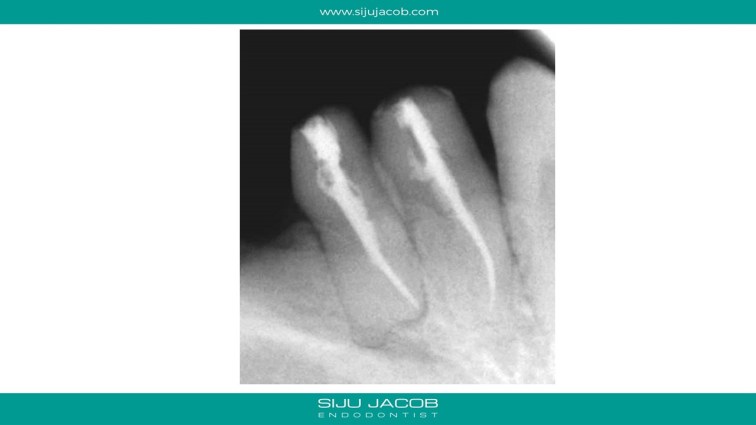

Endo and crowns were done by a general practitioner, after which the patient developed pain and tenderness. I Re-treated both teeth and placed fiber posts to strengthen the hollowed out coronal portion.